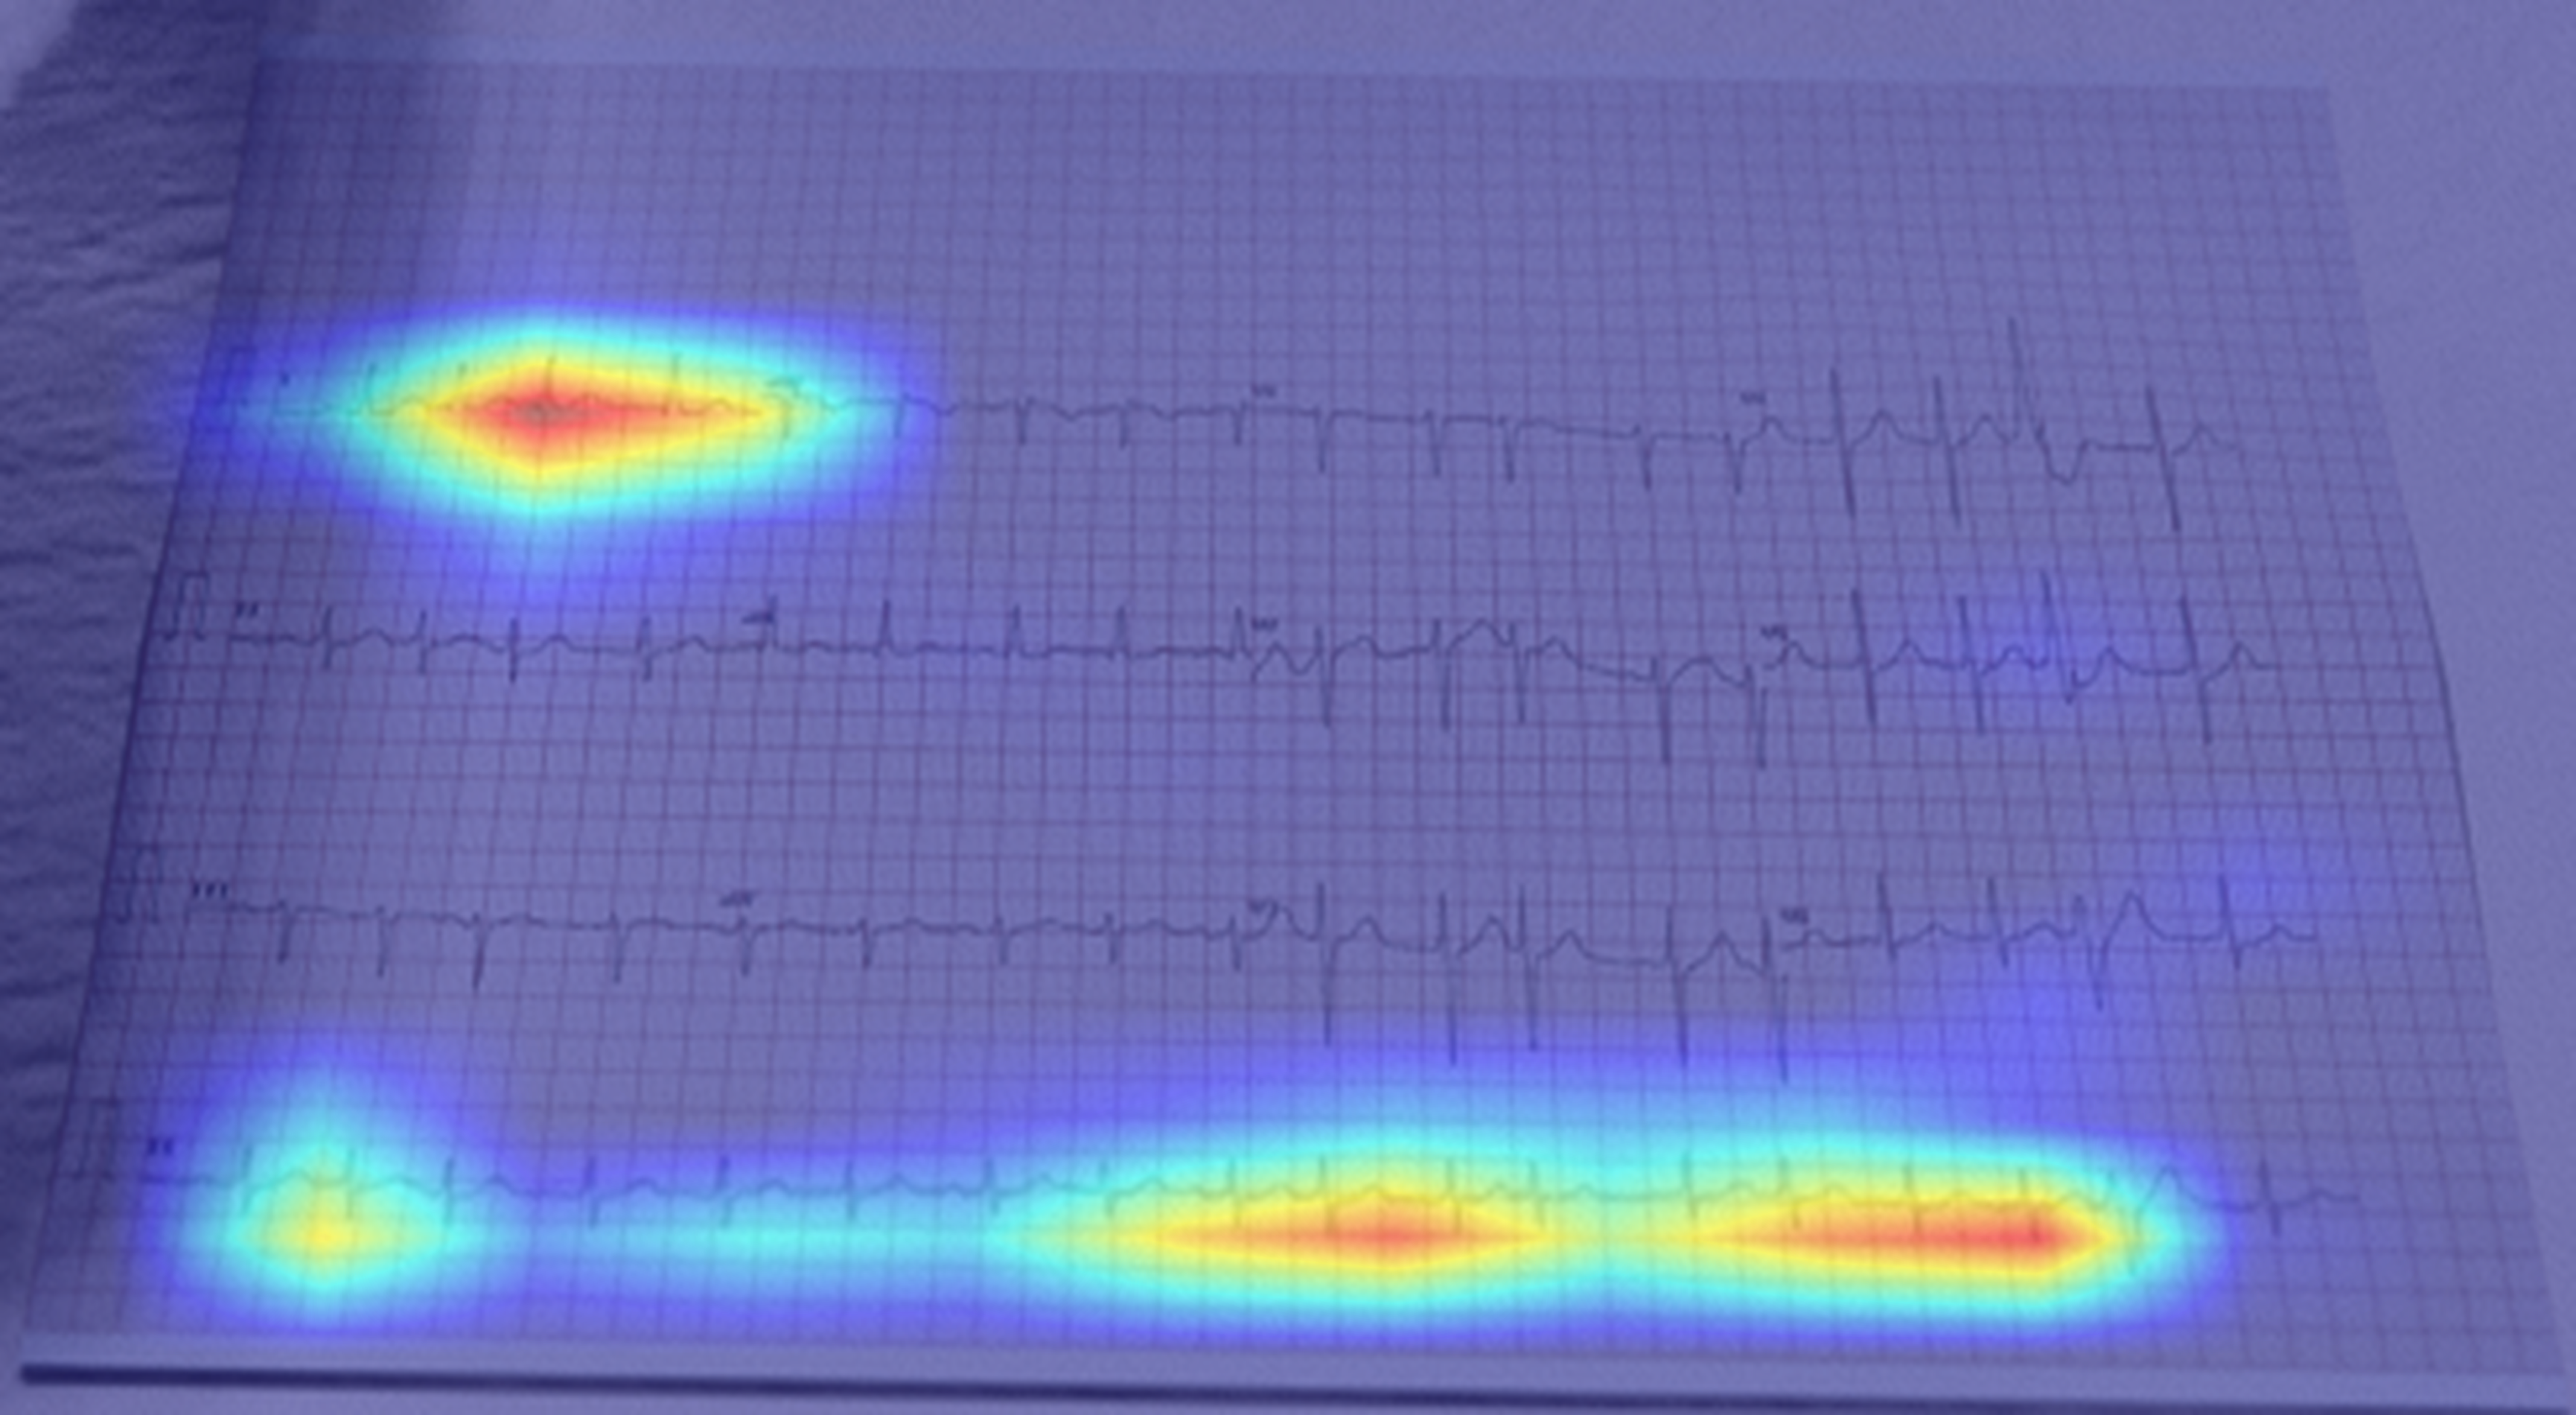

The Grad-CAM visualisations (Fig. 5) show that different pre-processing methods encourage the model to focus on different scales of information:

• 1.

ROI Crop + CLAHE preserves global context: Because this method retains the original layout and avoids aggressive transformations, the model processes the ECG as a continuous temporal signal. Figure 5b shows extended horizontal activation along the rhythm strip, indicating attention to temporal continuity. This is the appropriate strategy for detecting rhythm disorders such as Atrial Fibrillation (AF).

• 2.

Full Pipeline (Seg. + Rect.) emphasises local morphology: By segmenting and rectifying the image, this method enhances individual beats but reduces temporal information. As shown in Fig. 5c, the model concentrates on single-beat morphology. This benefits morphology-driven conditions such as Hypertrophy (Fig. 5f), but weakens rhythm analysis, resulting in lower performance on AF.

Refer to caption

(a) AF: Raw Input

(b) AF: ROI Crop + CLAHE

(c) AF: Full Pipeline (Seg. + Rect.)

(d) HYP: Raw Input

(e) HYP: ROI Crop + CLAHE

(f) HYP: Full Pipeline (Seg. + Rect.)

Figure 5: Grad-CAM visualizations for different pre-processing strategies on two samples: Atrial Fibrillation (AF, Top Row, a-c) and Hypertrophy (HYP, Bottom Row, d-f). (a, d) The Raw Input setting focuses on background noise. (b, e) The ROI Crop + CLAHE model shows a balanced focus that includes rhythm, which is the correct strategy for AF (b). (c, f) The Full Pipeline (Seg. + Rect.) model strongly prioritizes single-beat morphology. While this morphological focus is accurate for HYP (f), this bias toward morphology is less effective for the rhythm-based disorder AF (c).